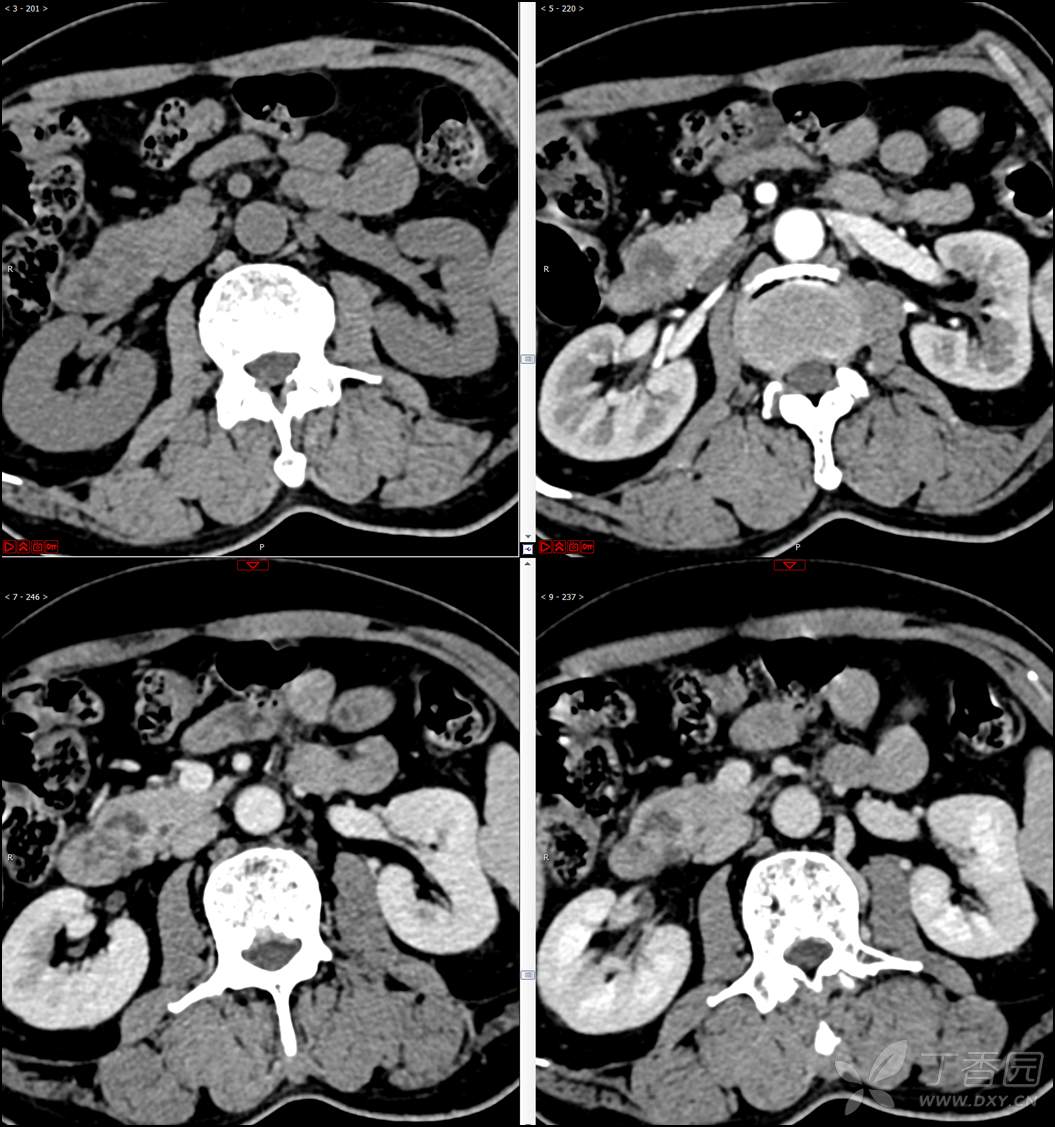

【影诊笔记521】老年男性,黑便就诊,请分析~『回帖即可查阅答案』

患者年龄:67岁

主诉:黑便1周。

现病史:患者1周前无明显诱因出现黑便伴头晕、心慌,无胸闷、胸痛,后仍间断黑便,2022-10-27就诊于某市中医院,行胃镜检查示:十二指肠溃疡伴出血,给予止血、抑酸等对症治疗,效果欠佳。今为行进一步治疗就诊于我院急诊,门诊完善新型冠状病毒核酸检测后以“十二指肠溃疡伴出血”收入我科。患者自发病以来,神志清,精神可,未进食,睡眠可,小便未见异常,黑便,近期体重无明显增减。